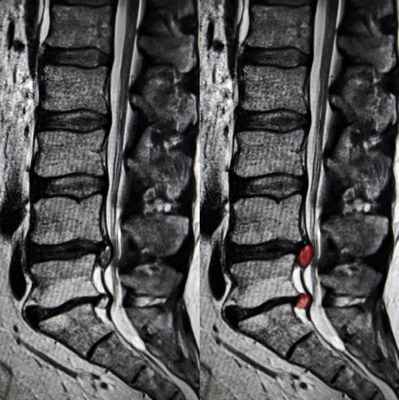

Что такое грыжа Шморля?

Грыжа Шморля — это разновидность грыжи позвоночного столба, которая проявляется продавливанием хрящевой ткани замыкательных пластин в кость тела соседнего позвонка. При этой патологии нет выпячивания, и она не всегда сопровождается болями, дискомфортом. Иногда эту грыжу называют «узелком Шморля» или «хрящевым узелком Шморля».

- в теле позвонка - хрящевые узлы (грыжа Шморля)

Что такое грыжа Шморля

Грыжу Шморля не нужно путать с межпозвонковой грыжей. Классическая грыжа имеет тенденцию к горизонтальному выпадению. Уходя в полость спинного мозга, она прижимает его и затрагивает корешки спинного мозга. От это возникают болевые ощущения у больного. Грыжа Шморля ведет себя по-другому. При ней поврежденный межпозвоночный диск попадает в само тело позвонка как вверх, так и вниз, а не вправо или влево. Чаще всего эта аномалия возникает в детском или подростковом возрасте, когда скорость роста мягких и костных тканей не согласованы друг с другом. Ребенок быстро растет, поэтому в позвонках образуются пустоты. В эти полости может сместиться пульпозное ядро диска. Также иногда грыжа Шморля может возникнуть при микротравмах позвоночника. Увидеть эту девиацию невролог может на МРТ снимке позвоночника. Как такового лечения это расстройство не требует, но нуждается в регулярном мониторинге, так как человек с такими изменениями имеет более высокие риски компрессионного перелома позвоночника.